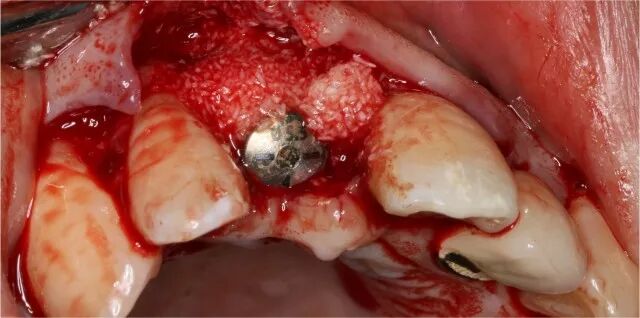

植骨

覆蓋吉特瑞

使用鈦釘增加垂直骨高度

植骨并覆蓋GBR膜

二期植入種植體